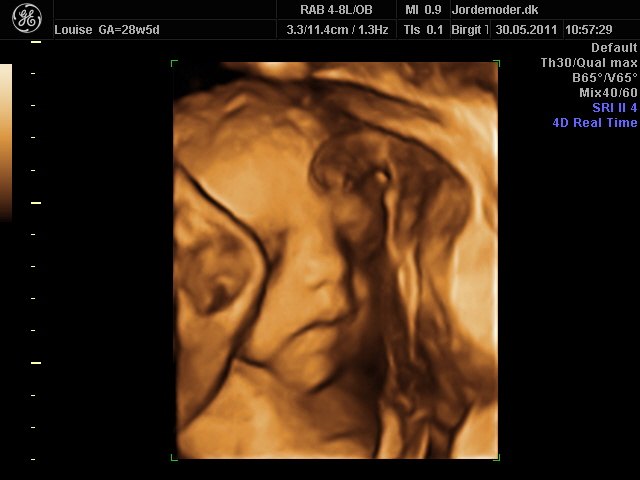

Moar2011

i uge 28

Vedhæftede fotos (klik for at se i fuld størrelse)